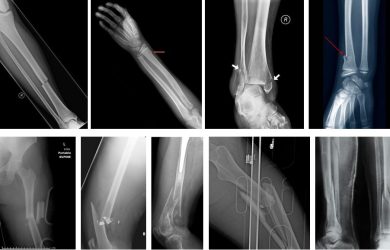

Остеосинтез при переломах трубчатих кісток, білясуглобові та внутрішньосуглобові переломи

- Сучасний остеосинтез переломів довгих кісток кінцівок